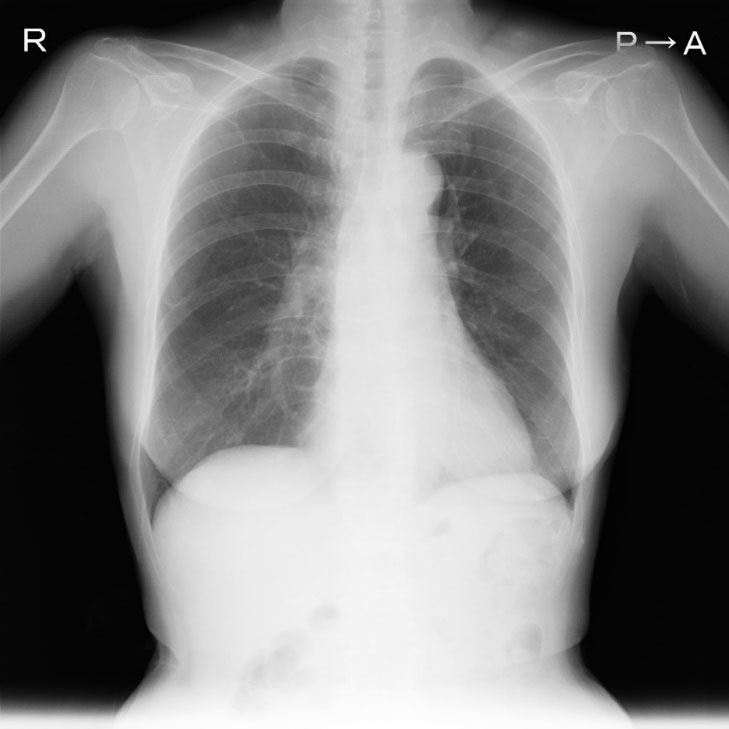

ペースメーカ等の不整脈デバイス治療の手術件数は全国で年間6万件以上が行われており、デバイス治療に関連した合併症も散見され、特に感染を合併した際にはリードを含めたすべての異物除去が必須であることは広く認知されています。

デバイス感染が起きると敗血症や感染性心内膜炎などを起こす恐れもあるため、リードを抜き取る必要があります。リードは植え込まれている年数が長い場合は、静脈や心臓の壁に癒着を起こし牽引しても抜けない状態になります。過度の牽引は血管損傷や穿孔といった致死的な合併症を引き起こす可能性が高く、開胸手術による摘出が行われていました。

リード抜去は心タンポナーデ、鎖骨下と上大静脈の血管損傷や血気胸などの重篤な合併症があり、すぐに開胸して止血術を行わなければならないために心臓血管外科の待機下で施行が必要です。